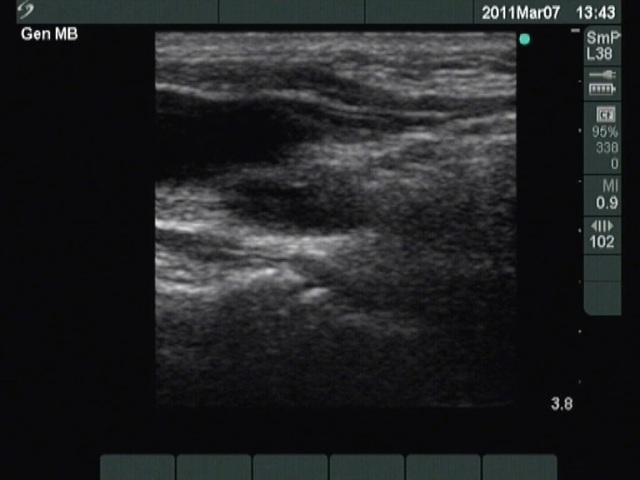

Ultrasound. Except for inconspicuous, moderately hypoechogenic lesion on the ventral wall of the carotid artery, neither thyroid parenchyma in the thyroid beds nor suspicious neck lymph nodes were found. The moderately hypoechoic lesion has bright echogenic granules and was avascular.